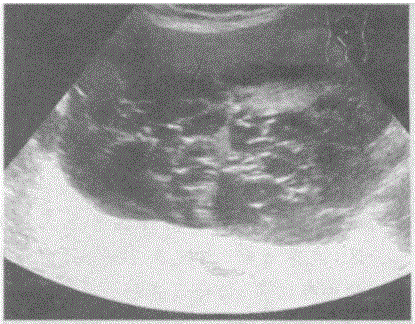

问题 临床资料:女,69岁,自诉下腹部疼痛,排便困难。 临床物理检查:右下腹可扪及一肿物,质硬,边界清,活动度好,有压痛。 超声综合描述:子宫前位,形态大小如常,肌壁回声均匀,内膜厚度0.3cm。腹、盆腔可见无回声区,上界平脐,下至耻骨联合,形态不规则,内呈网状,分隔多且厚薄不均,CDFI:分隔上可见条状血流信号,PW:呈动脉频谱,RI=0.54。

选项 A.腹盆腔多房囊性占位(卵巢癌) B.畸胎瘤 C.腹盆腔结核 D.腹盆腔包裹性积液

答案 A